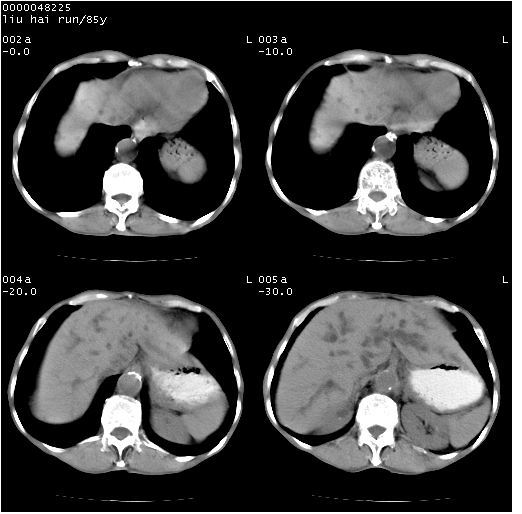

标题: CT13403:M,85Y。胆系低位梗阻。胰头占位? [打印本页]

标题: CT13403:M,85Y。胆系低位梗阻。胰头占位?

彩超示胰头实质欠均匀,胰管扩张。

影像表现:壶腹部扩张胆管呈截断样改变,肝内外胆管重度扩张,胆囊增大,胰管亦明显扩张,呈不规则患珠样,胰体尾部略有萎缩,增强扫描后壶腹部低密度影轻度强化,与钩突分界不清。

ct诊断:胆管癌。鉴别诊断:胰腺癌,胰腺癌为少血供肿瘤,增强后强化不明显,静脉期及延时后与正常胰腺分界清晰。

1)胆系低位梗阻(肝内外胆管扩张、胰管扩张、胆囊增大);考虑为:胰头癌可能性大,不排除胆总管下端癌。2)双肾多发囊肿。